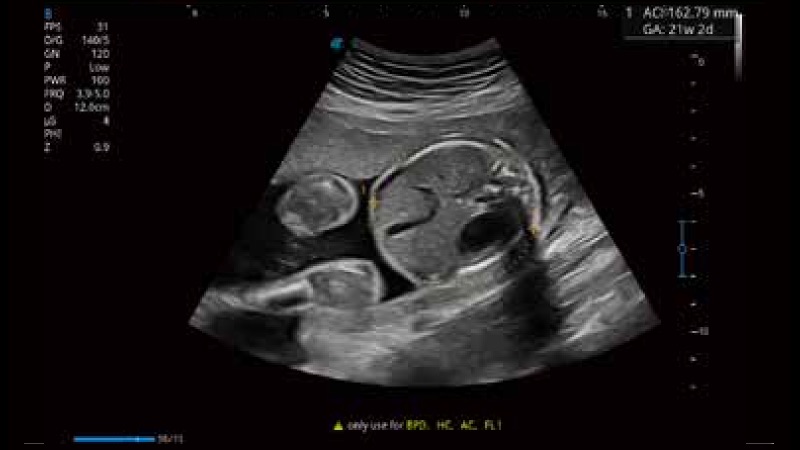

容积探头

凭借狗万官方网站先进的成像技术和优异的探头技术提供的清晰的图像表现,您可以更自信地做出临床决策。